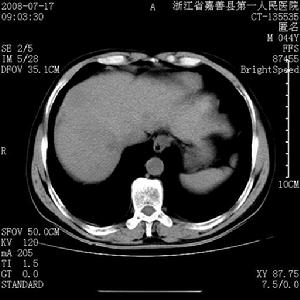

(二)腦瘤 CT對腦瘤的定位定量診斷相當可靠,定性也優於其他方法,三、四代CT對直徑不小於0.5cm的病灶亦能清楚顯示。根據顯影病灶的位置和腦室、腦池的改變多不難確定腫瘤位置,結合冠狀面與矢狀面的圖像重建,可顯示出腫瘤在三維空間的位置,使定位診斷更為準確。

常見腫瘤多有典型的CT表現,70~80%的病例可做出定性診斷。例如,腦膜瘤多表現為高密度、邊界清楚、球形或分葉狀病灶,且與顱骨或小腦幕或大腦鐮相連。增強後明顯強化。腦轉移瘤多在皮層及皮層下區,呈小的低、高或混雜密度病灶,增強後呈環狀強化或均勻強化,病灶多發對診斷意義較大。鞍上低或混雜密度病灶,有增強多為顱咽管瘤。聽神經瘤為橋小腦角區低或稍高密度病灶,有增強,同時可見內聽道擴大與破壞。顱內腫瘤的特徵性徵象為瘤體周圍組織廣泛水腫,鄰近腦結構及中線結構的偏移。位於腦中線處腫瘤尤其是顱後窩腫瘤,即使瘤體較小亦可引起中重度的腦積水徵象,由於常見腫瘤有時出現不典型CT表現,而一些少腫瘤還可出現常見腫瘤的典型表現,致使CT對顱內腫瘤的定性診斷受到局限。